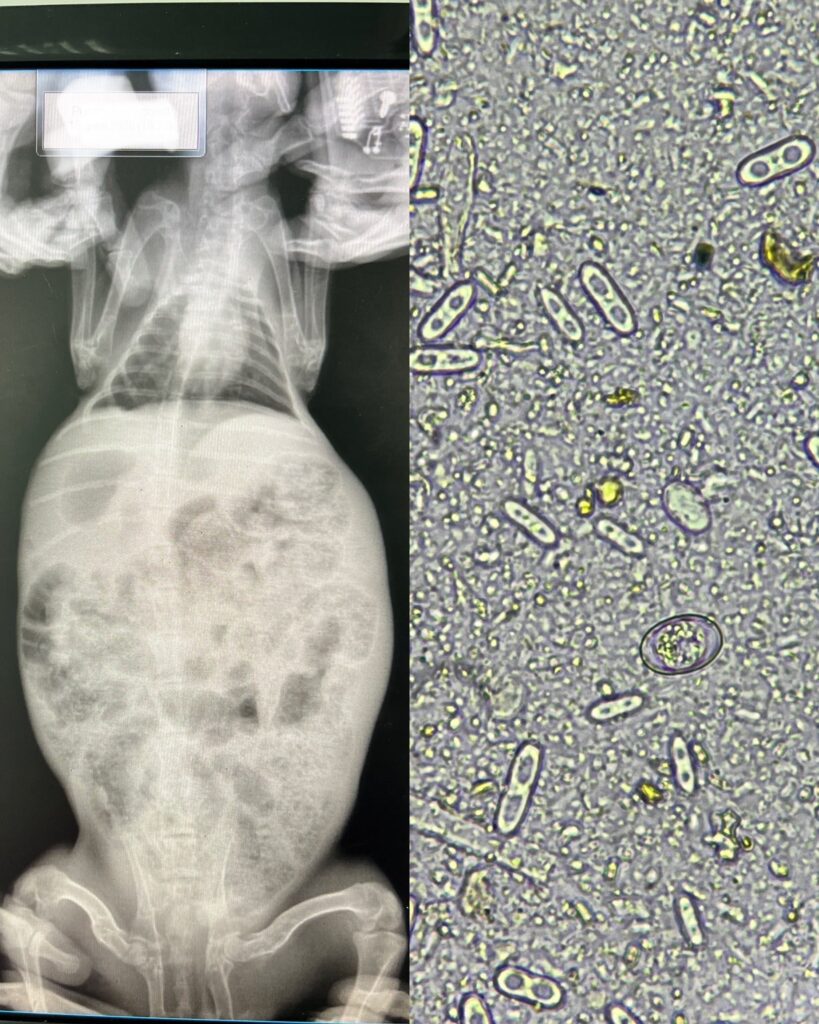

Дальнейшая диагностика – рентгенография и микроскопия кала выявили сильнейшую инвазию простейшими разных видов. Ветеринарный врач боролся за жизнь зайчика несколько часов, состояние питомца менялось как качели, то он начинал реагировать, то снова ложился без чувств. Ночью у владельцев зайчик пал. Очень жаль, что не успели спасти малыша. Диспансеризация – это шанс питомцу на счастливую, здоровую жизнь, а не вытягивание денег из владельцев. Чем раньше выявлено любое заболевание, тем выше шанс спасти без осложнений вашего питомца, помните об этом!